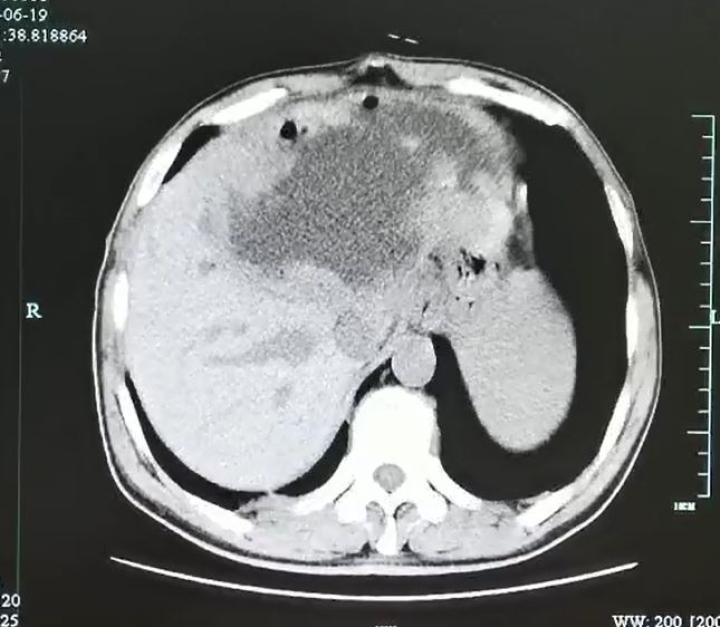

入院后腹部CT检查发现肝脓肿壁上长了很多肿瘤样的结构,而且壁很厚。看来这个肝脓肿不简单。

为了让脓球变小,进一步追查“元凶”,医生在超声指引下给谢师傅做了脓球的穿刺引流。结果大量的灰白色脓液被顺利引出,但是经过一系列的检查后,却没有发现细菌、真菌、结核和恶性肿瘤的“踪迹”。那谢师傅到底得了什么病呢?

经过肝胆外科、感染科、影像科等多学科会诊及讨论后,贾长库主任、沈伟敏主任医师、徐孙兵副主任医师等,果断地为患者进行了手术将左半肝切除,完整地拿掉了这个迷雾重重的病灶。